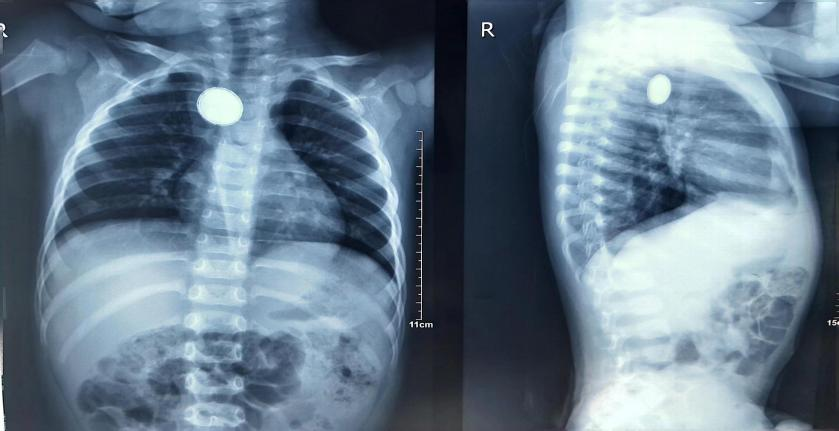

三个月前,1岁7月龄的浩浩因“反复呛咳剧烈,频发恶心呕吐”,在当地治疗效果不佳后转入北大医院宁夏妇儿医院,检查结果令人震惊——食管异物,一个贰分硬币大小的金属异物卡在患儿的食道中段!由于异物在孩子体内滞留时间过长,已经出现了压迫症状,小浩浩被送来时已奄奄一息,生命亮起了红灯。

终于,经过从方案制定到取出异物这紧张忙碌的一个小时后,只听“咣当”一声,孩子体内的异物经内镜成功取出后掉落在弯盘中,原来是一枚纽扣电池!

纽扣电池,被称为食道异物罪恶之最,它不仅会对食道进行压迫伤害,其自身的化学物质也会对机体组织产生持续性腐蚀。由于这枚电池在浩浩食道内滞留过久,表面已经出现斑驳锈迹,从镜下看,孩子的食道黏膜整体呈现暗灰色,溃疡遍布,没有了组织该有的生机。